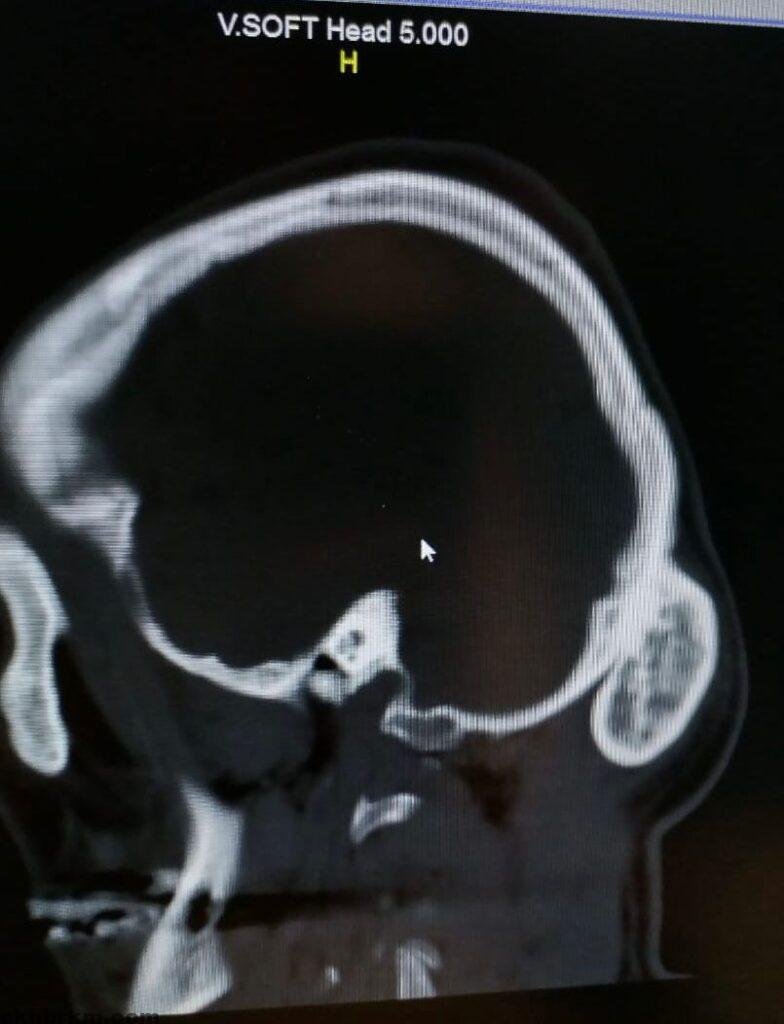

وقال الفريق الطبي بانه فور وصول المريض أجريت له كامل الفحوصات المخبرية والمقطعية على المخ واشعة ثلاثية الابعاد حيث تبين وجود ورم حميد في القشرة الخارجية من عظام الجمجمة.

وأشار الفريق الطبي بانة تم ادخال المريض الى غرفة العمليات واجراء تدخل جراحي تم خلاله استئصال الورم الذي يزن حجمه ( ٣٠٠ جرام ) وبفضل الله تكللت العملية بالنجاح بعد ان استغرقت أكثر من ساعة ونصف ويتمتع بحالة صحية جيدة حاليا ومازال تحت الملاحظة الطبية.